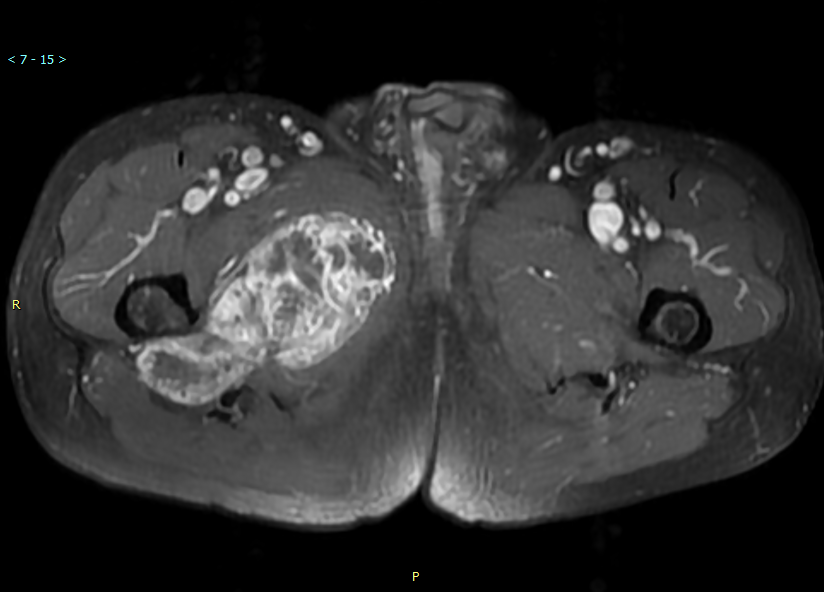

CT+增强 T1WI

T1WI T1+增强

MR所见:右大腿上段长收肌内侧肌间隙内见不规则肿块影,T1WI以等低信号为主,其内见斑片状稍高信号影,增强扫描肿块实性部分及纤维分隔明显强化,呈蜂窝状,邻近肌群受压推挤,局部见脂肪分离征,肿块钻缝生长。

MRI :图像上多表现为分叶状肿块,由于特征性软骨基质的存在,T1WI 呈等或低信号 ( 与肌肉相比) ,肿瘤伴有出血坏死时信号复杂, T2WI 呈混杂高信号,病灶中心的信号强度更高,内可见低信号间隔,把肿瘤分成多个小叶,增强扫描可见间隔强化。